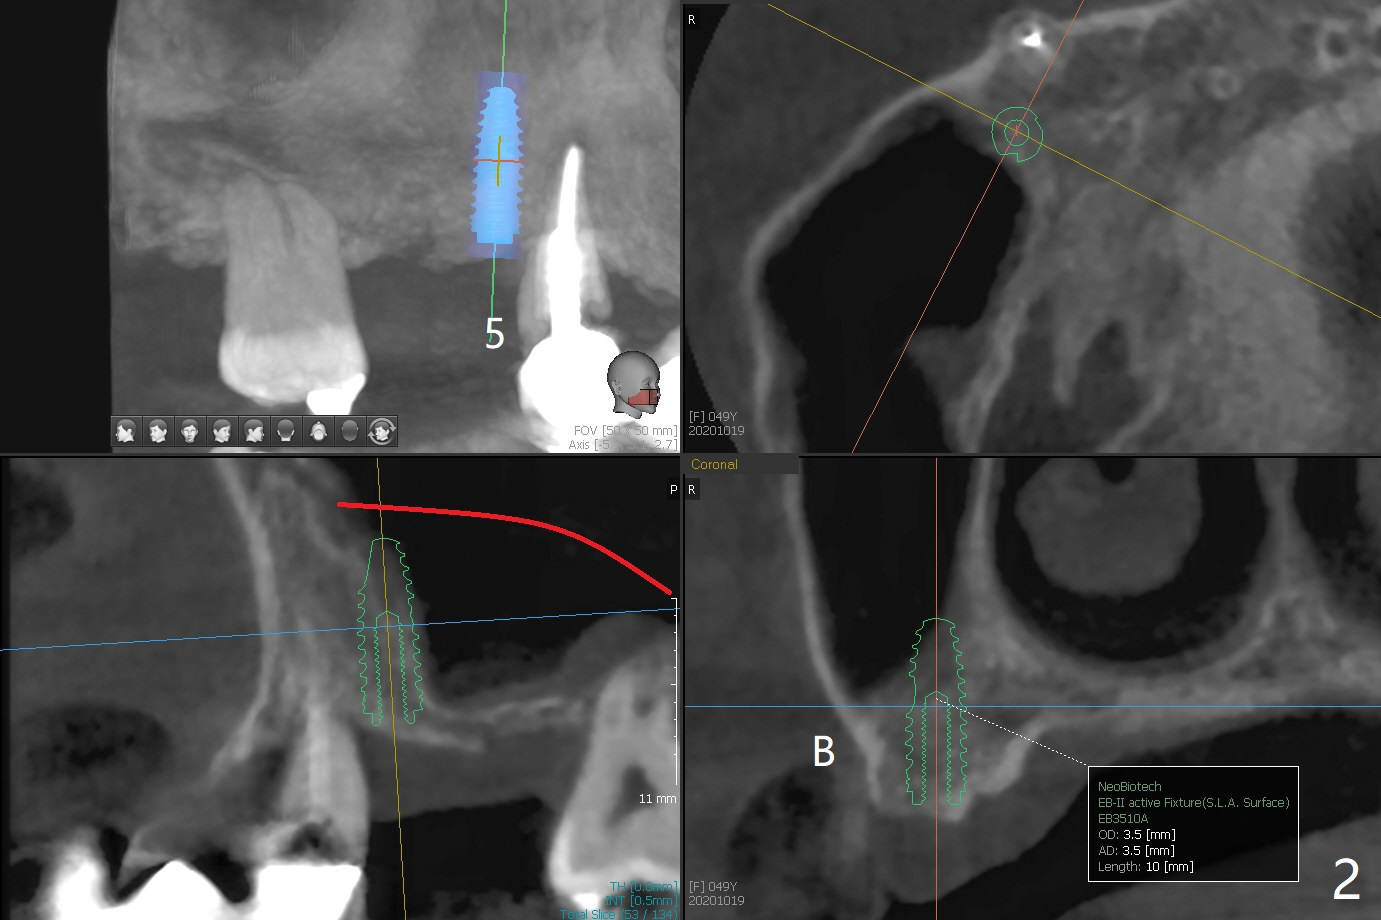

49岁女(图一)同意先做右上5,6种植(图二,三),但是必须先做外提升,高至5根尖(图二:红线),范围延申至右上7,后者骨质吸收厉害(图三:*),预后不佳。后者可能是好几年的事情,是杞人忧天?准备DIO Sinus Master Kit, sinus curettes (curved), a round flat osteotome (in sinus box) and mallet as well as PRFx2。图三黄线代表外提升入口。外提失败因为遇到动脉(图四),上牙槽中血管穿过上颌窦前壁(图五)。实验室建议在右上5种植(图六至八)。结果内提同期种植。